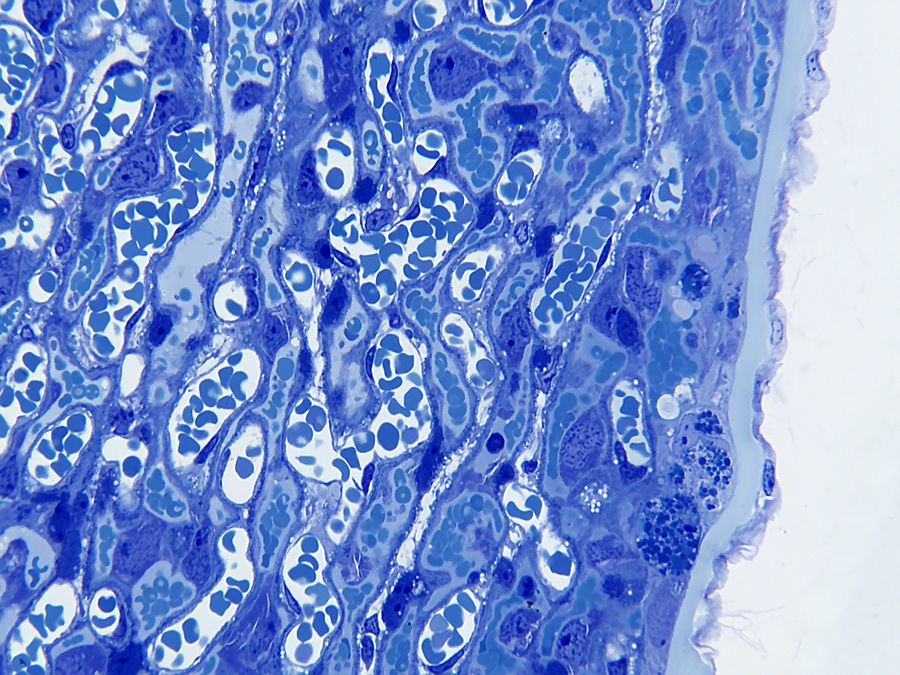

De decidua wordt van de embryonale labyrintische zone gescheiden door de junctionele zone. De junctionele zone bevat maternale bloedvaten (veneuze drainage), trofoblastreuscellen en spongiotrofoblastcellen. Trofoblastcellen zijn over het algemeen erg groot met bizar gevormde of meervoudige kernen. Reusceltrofoblasten zijn, zoals hun naam al zegt, erg groot - tot 100 µm in diameter en bevinden zich het dichtst bij de decidua. Spongiotrofoblasten zijn fagocytisch[6] en kunnen gefagocytiseerde erytrocyten bevatten en bevinden zich dichter bij de labyrintische zone. De labyrintische zone bestaat uit nauw tegenover elkaar liggende foetale en maternale bloedkanalen. De foetale bloedkanalen zijn bekleed met dunne endotheelcellen en bevatten grote onrijpe gekerfde rode bloedcellen, terwijl de maternale bloedkanalen bekleed zijn met grote labyrintische trofoblastcellen.

De muis heeft een hemochoriale placenta waarbij maternaal bloed in contact staat met foetaal chorion via een labyrintische laag (mensen hebben een vergelijkbaar type placentatie). De placenta bestaat uit maternale en embryonale lagen. De van het moederdier afkomstige laag is de decidua, die zich ontwikkelt uit het endometrium. De decidua bestaat uit twee delen: de decidua basalis en de decidua capsularis. De basalis heeft een rijk vasculair netwerk en bestaat uit losjes aanhangende onregelmatige grote vacuolate cellen met verschillend gevormde kernen van verschillende grootte.